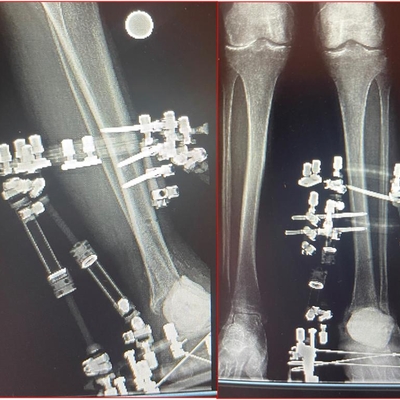

Click on an image below to view more info.